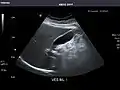

Kidneys: Right and left kidneys measure 11.5 cm and 12 cm in length respectively. No hydronephrosis. Small left lower pole kidney cyst.

Left kidney